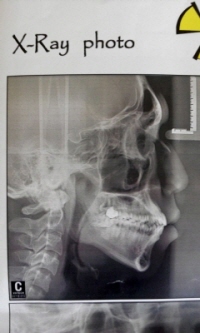

1.제 정밀사진보면요 위턱 앞니가 아래턱 앞니 보다 나와있는경우인데요 (검색해보니2급 부정교합 인거같네요)

2.그리고 교정 전후 사진들 여기저기 많이보면요 다 다르더라구요. 저도 보니 잇몸돌출+치아돌출같은데 맞나요 잇몸돌출이 심한가요?

4 .마지막으로 무턱문제인데요. 이게 후기들에 정밀사진들도 같이있으면 저랑 정도를 비교하며대충 가늠 할텐데.. 정밀사진을 볼수있는곳없어서 예상결과 예측하기가힘들어요

저정도면 교정 끝나고 외관상으로 무턱 완전히 해소될수있는지요

(제 정밀사진과 현재 옆모습, 제가 이상적으로 생각하는 옆모습 올립니다 (교정만으로 비슷한느낌까지 갈수있을지요

현재 사진이구요, 당기기 한달정도됬는데 별변화모르겠네요..

현재 사진이구요, 당기기 한달정도됬는데 별변화모르겠네요..입술에 긴장하고찍어서 저렇게 돌출이 약해보이는데 힘다풀고 찍으면

정밀사진에서 보시는것처럼 뚱한인상이 있는 그런정도입니다

->>사진 본문에 쓴것들 차례대로입니다.

정밀,당기기한달차, 제가 이상적으로생각하는 옆모습